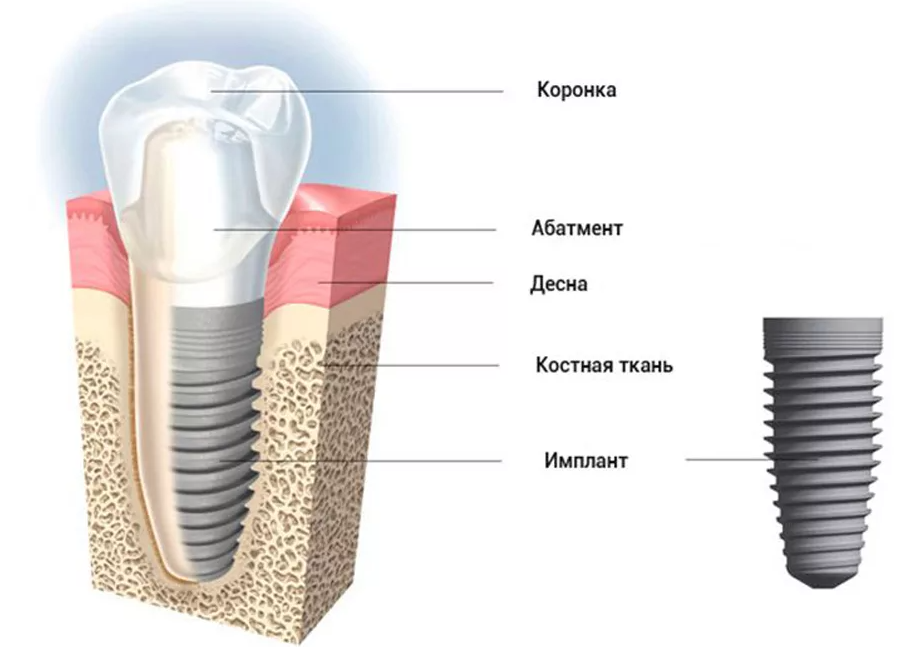

Как устроены дентальные импланты

Современные импланты состоят из нескольких частей:

- Штифта (имплант);

- абатмента;

- коронки.

Штифт изготавливается из титана и выполняет роль нового корня зуба. Медицинский титан, который применяется для его изготовления, не отторгается. На корне присутствует резьба для установки в челюсть. Успешная имплантация зубов гарантирована в 99% случаев. При процедуре остеоинтеграции учитывают такие факторы, как возраст пациента, состояние здоровья, объем костной ткани в месте установки, количество зубов, которые нужно возместить. Учитывается и общее количество отсутствующих зубов в челюсти.